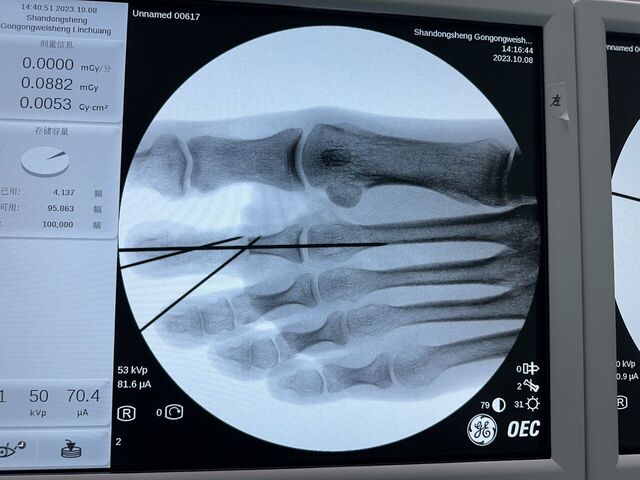

今天的环指再造

微信图片_20231008195909.jpg 微信图片_20231008195912.jpg 微信图片_20231008195906.jpg 微信图片_20231008195903.jpg 微信图片_20231008195839.jpg 微信图片_20231008195829.jpg 微信图片_20231008195945.jpg 微信图片_20231008195939.jpg